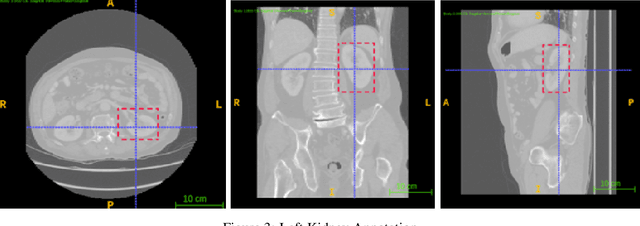

Abstract:Computer aided diagnostics often requires analysis of a region of interest (ROI) within a radiology scan, and the ROI may be an organ or a suborgan. Although deep learning algorithms have the ability to outperform other methods, they rely on the availability of a large amount of annotated data. Motivated by the need to address this limitation, an approach to localisation and detection of multiple organs based on supervised and semi-supervised learning is presented here. It draws upon previous work by the authors on localising the thoracic and lumbar spine region in CT images. The method generates six bounding boxes of organs of interest, which are then fused to a single bounding box. The results of experiments on localisation of the Spleen, Left and Right Kidneys in CT Images using supervised and semi supervised learning (SSL) demonstrate the ability to address data limitations with a much smaller data set and fewer annotations, compared to other state-of-the-art methods. The SSL performance was evaluated using three different mixes of labelled and unlabelled data (i.e.30:70,35:65,40:60) for each of lumbar spine, spleen left and right kidneys respectively. The results indicate that SSL provides a workable alternative especially in medical imaging where it is difficult to obtain annotated data.